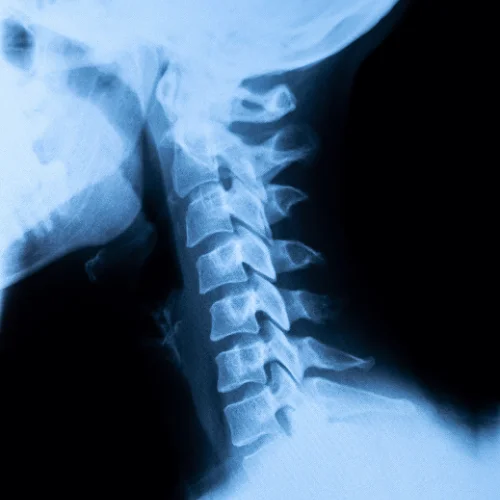

We will review your x-ray findings, answer any additional questions you may have, and discuss your current healthcare goals during your second chiropractic visit. The visit will generally take about 30 minutes. A care plan with follow-up visits will be determined based on your goals and the outcome you desire.